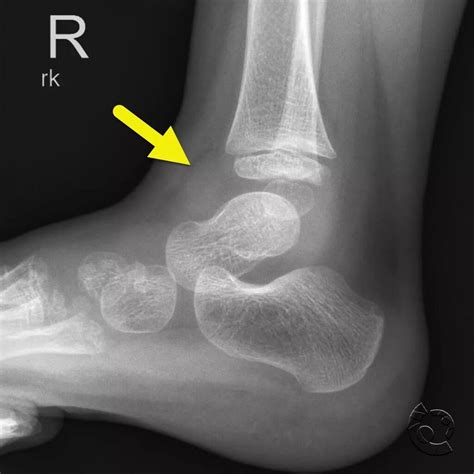

A Lateral Foot X Ray is a type of radiographic imaging that captures a side view of the foot. This view is essential for evaluating the alignment and integrity of the bones, joints, and soft tissues in the foot. Unlike an anteroposterior (AP) view, which provides a front-to-back image, a lateral view offers a different perspective that can reveal issues not visible in other projections.

Interpreting a Lateral Foot X Ray

Interpreting a lateral foot X ray requires a trained eye and knowledge of foot anatomy. Here are some key points to consider:

• Bone Density: Assess the density and clarity of the bones. Abnormalities in bone density can indicate conditions like osteoporosis or bone tumors.

• Bone Alignment: Check the alignment of the bones, particularly the calcaneus, talus, and metatarsals. Misalignment can indicate fractures, dislocations, or deformities.

• Joint Spaces: Evaluate the joint spaces for any narrowing or irregularities, which can suggest arthritis or other joint diseases.

• Soft Tissue: Look for any abnormalities in the soft tissue, such as swelling, calcifications, or foreign bodies.

Common Findings in a Lateral Foot X Ray

A lateral foot X ray can reveal a variety of conditions and abnormalities. Some of the most common findings include:

• Fractures: Fractures of the calcaneus, metatarsals, or other foot bones can be clearly seen in a lateral view.

• Arthritis: Joint space narrowing, bone spurs, and other signs of arthritis can be identified.

• Deformities: Conditions like flatfoot, high arches, or bunions can be evaluated.

• Foreign Bodies: Objects embedded in the foot, such as glass or metal, can be detected.

• Soft Tissue Abnormalities: Swelling, cysts, or other soft tissue issues can sometimes be seen.